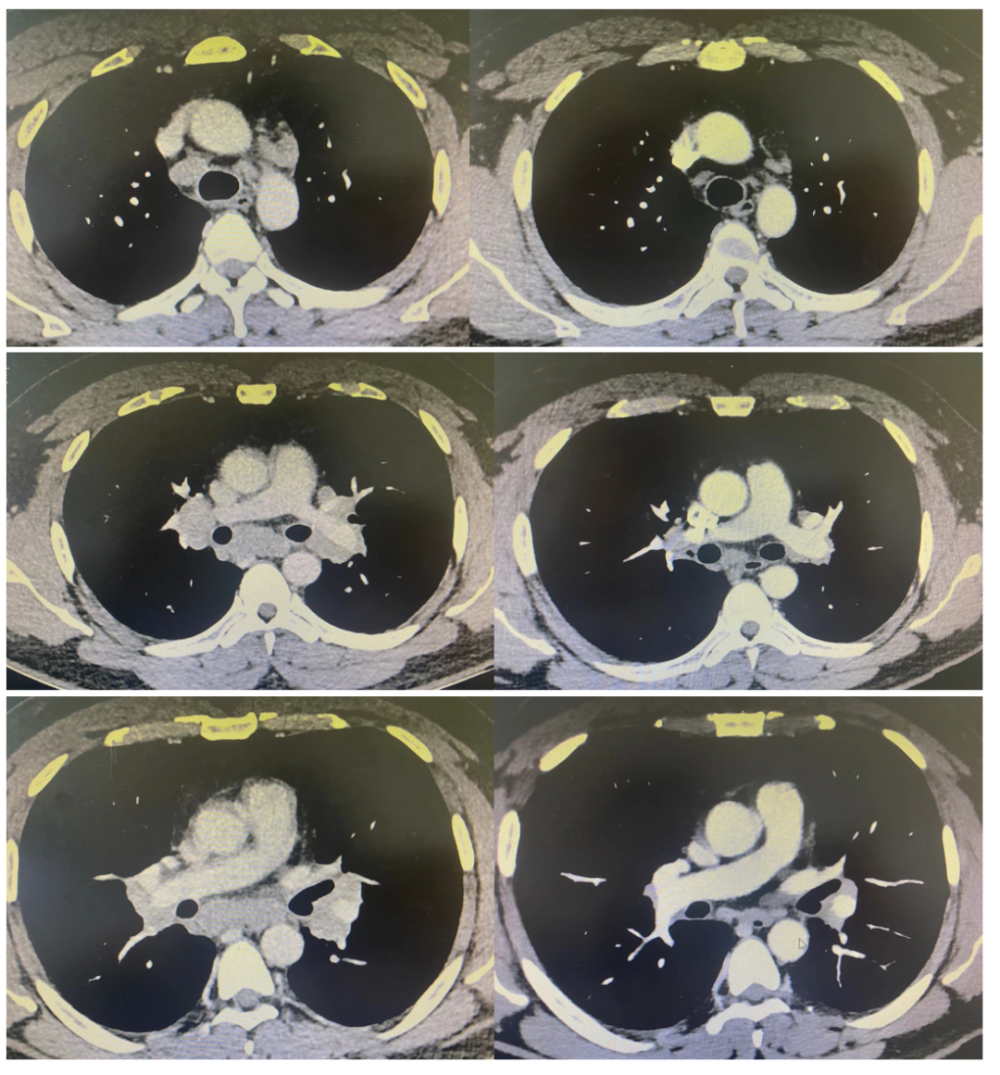

丁香园论坛>影像核医学>帖子详情>3600_1800

图片尺寸3600x1800

【影像读片】右肺门增大,随访有结果(结果已公布)